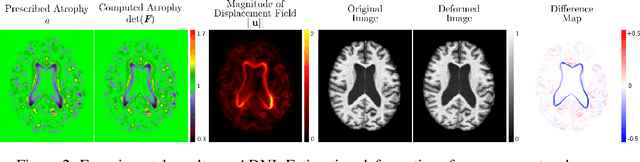

Abstract:We present a proof-of-concept, deep learning (DL) based, differentiable biomechanical model of realistic brain deformations. Using prescribed maps of local atrophy and growth as input, the network learns to deform images according to a Neo-Hookean model of tissue deformation. The tool is validated using longitudinal brain atrophy data from the Alzheimer's Disease Neuroimaging Initiative (ADNI) dataset, and we demonstrate that the trained model is capable of rapidly simulating new brain deformations with minimal residuals. This method has the potential to be used in data augmentation or for the exploration of different causal hypotheses reflecting brain growth and atrophy.